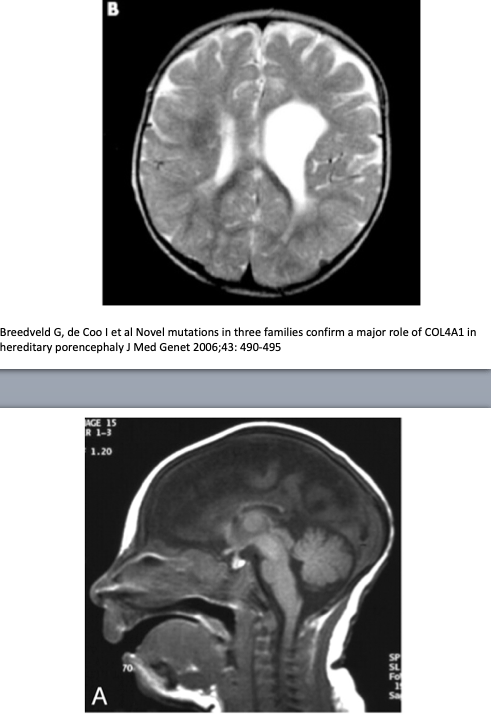

If the myelination pattern does not concur with the calender age, there can be hypomyelination or dysmyelination, meaning that not enough myelin is formed. Leukodystrophy is a term used for rare disorders involving (mainly) white matter with an underlying genetic, metabolic cause and symmetrical involvement as a key MRI finding(47-52). In demyelinating disorders there is destruction of previously formed myelin. The most known and prevalent demyelinating disease is not a leukodystrophy but an inflammatory one: multiple sclerosis, with a specific pattern of (non-symmetrical) white matter abnormalities on MRI located periventricular, in the corpus callosum, juxtacortical and infratentorial (39).